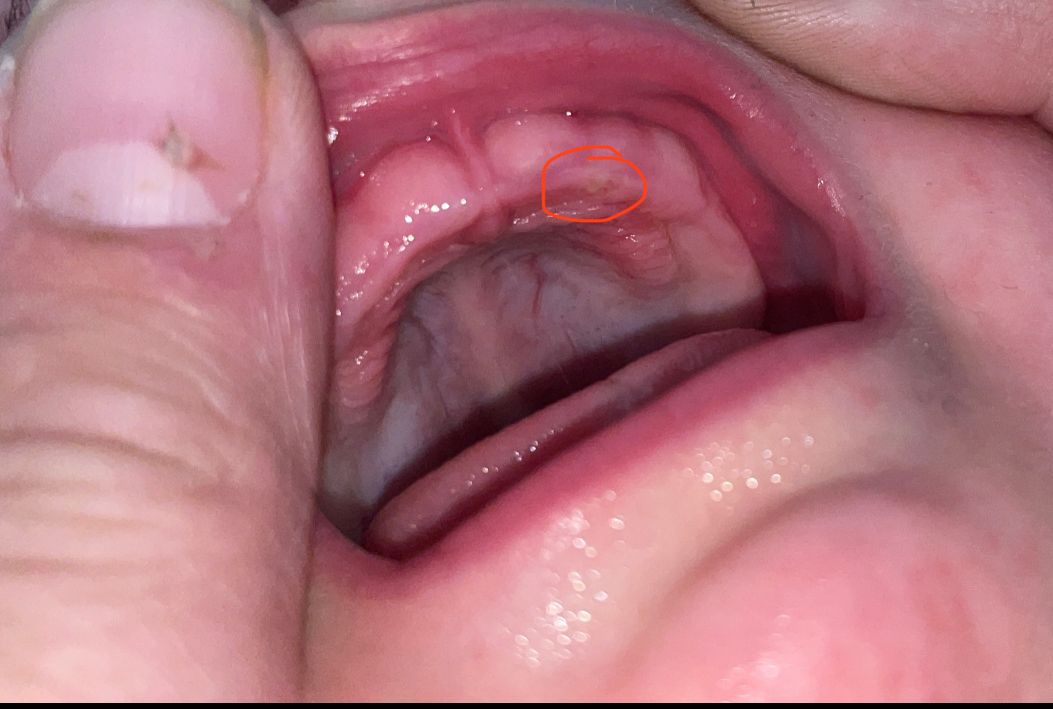

Habe heute bei meinen sieben Monate alten Sohn diese Stelle oben am Zahnfleisch entdeckt.

Er hat keine Schmerzen. kein Fieber. Die Stelle ist nicht wulstig oder überhaupt mit dem Finger zu spüren. Daher sehe ich von einem Besuch in der Rettungsstelle ab. Bin allerdings etwas beunruhigt und frage daher hier nach.

ist eine kleine fistel, weil die oberen milchzähne bald durchbrechen werden, alles normal. lasse ihn weiterhin spielen und alles in den mund stopfen, dann wird er später gesund sein!